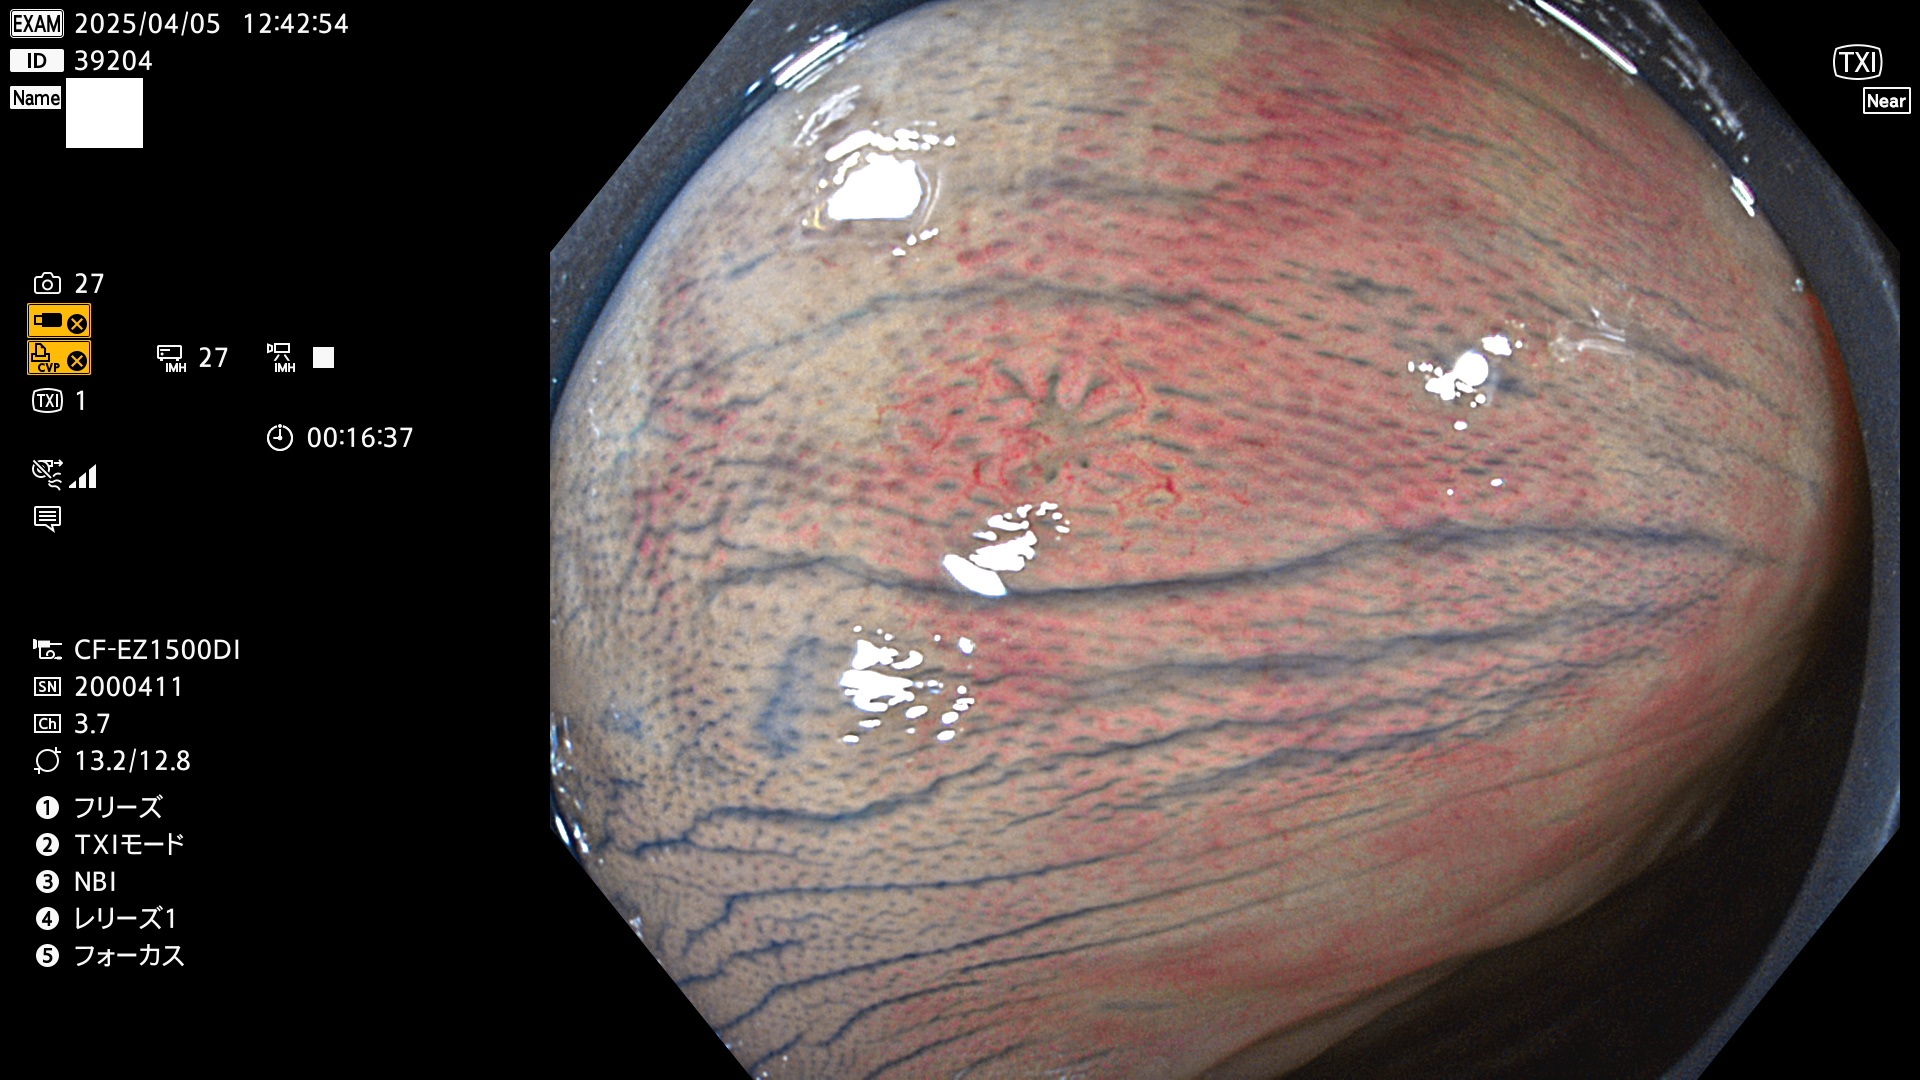

今週のUb、Uc型腺腫

完全に平坦な物をUb、陥凹している物をUcと呼びます。Ubは認識が困難で、Ucはびらん(炎症)と紛らわしいために見落とされやすく、「内視鏡後・大腸癌」の原因になります。

抽出の対象期間 2025年4月3日〜4月6日の4日間(48件の検査)4個 (4/48=8%)